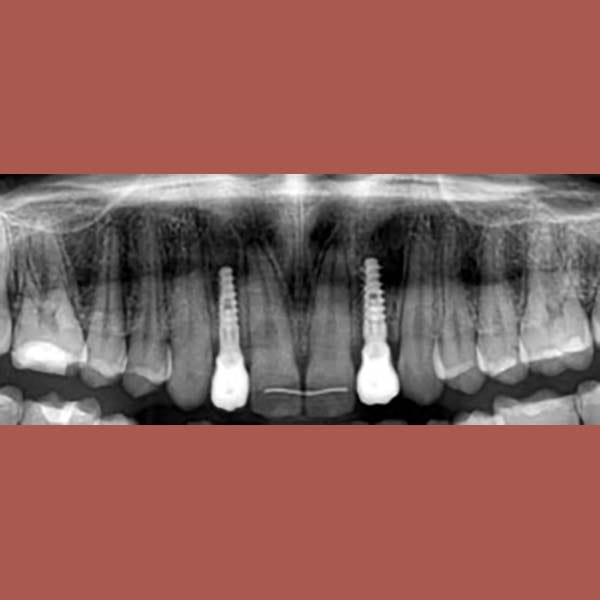

AFTER

عانت هذه السيدة من وجود عضة عميقة أمامية و غياب خلقي لسنين أماميين سفليين ،بالإضافة لتراكب و عدم ارتصاف الأسنان الأمامية العلوية بشكل جيد – تم فتح مسافة كافية لوضع غرستين سنيتين و تم تصخيح العضة العميقة تقويمياً